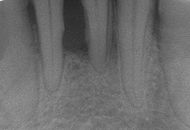

En este caso no sólo se afecta la encía si no también el resto de tejidos que sujetan el diente, como son el ligamento periodontal y el hueso alveolar; ésta es la principal característica diferencial con la gingivitis. Además se produce normalmente una separación entre la encía y el diente, que se denomina bolsa periodontal. Suele tener una profundidad de 4 o más milímetros.

Es clínico y radiográfico, al comprobar la existencia de bolsas con un instrumento específico denominado sonda periodontal, así como al observar la hemorragia, supuración gingival y ocasionalmente movilidad del diente. Radiográficamente se confirma al ver un nivel de hueso más bajo de lo normal.

Es muy importante una detección precoz, para así instaurar un tratamiento eficaz y evitar que la enfermedad siga avanzando. Salvo casos concretos el tejido periodontal perdido no se recupera.